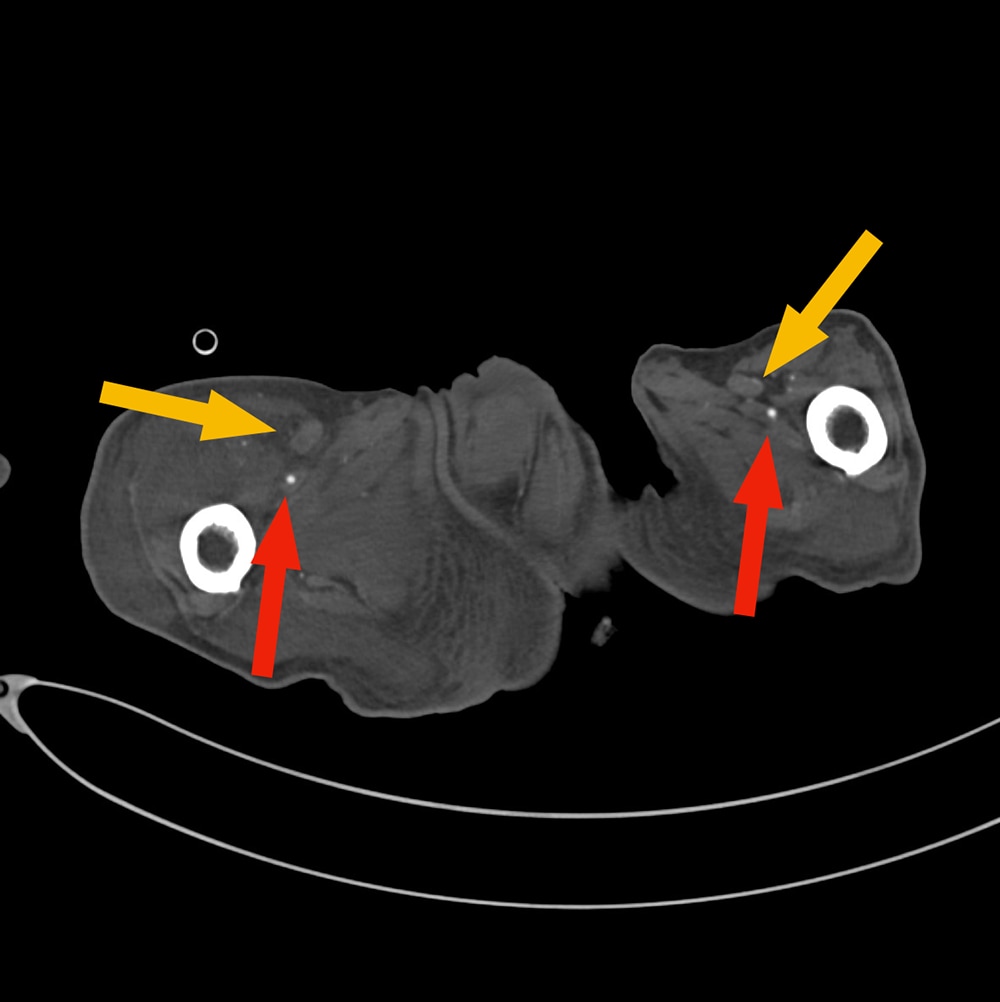

60代男性。高血圧、糖尿病、脂質異常症、喫煙など多数の既往がある。他院にて進行する下肢壊疽を認め、切断目的に当院に転院。入院1日目に下肢造影ダイナミックCTが施行された。動脈相で両側浅大腿動脈近位に閉塞を認めた。右下肢では側副路を介して膝窩~下腿三枝の細い描出が確認されたが、左下腿三枝の描出は認められなかった。左下腿の軟部組織は腫脹し、対側にくらべ造影効果の減弱と多量のガス像も見られたことから左優位の閉塞性動脈硬化症に伴う左下腿壊疽と診断した。感染コントロール困難で入院2日目に急変し死亡した。

下肢造影CTを撮像すると下肢動脈の狭窄形態や病変前後の血管走行、石灰化やプラークなど血管壁の性状評価、側副血行路の評価、多発病変の有無、その他に潰瘍病変、動脈瘤、解離の有無など非常に多くの情報を得ることができる。症例によっては遅延相を追加することで静脈の走行や位置関係の他、静脈内血栓の評価も行うことができる。さらに多断面再構成像や3次元像を構築することで血管の状態をイメージしやすくなり、その後の治療においてはカテーテルによる血行再建術のリファレンスとして使用するなど治療にも大変有用な検査と考えられる。治療後においては効果判定や合併症の有無、その後の経過観察に有用である。

注意点としては下腿三枝など特に細い血管では描出に限界があることや、石灰化と造影剤の区別が難しい場合があることなどが挙げられる。その他造影剤使用による一般的な合併症(アレルギーやアナフィラキシー、造影剤誘発性腎障害、被ばくのリスク、注入時の皮下漏れなど)は常に注意しておかなければならない。またアレルギーや腎機能障害などにより造影剤の使用が困難な場合もあるため、既往歴などを確認し、リスクベネフィットを鑑みて検査を行うことが肝要である。